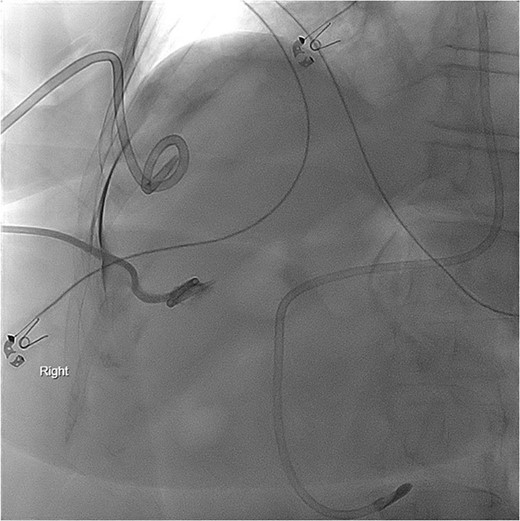

Repeat imaging was performed and revealed peri-hepatic ascites, significant anasarca and bilateral pleural effusions (Fig. 3) while the PCT remained in good position (Fig. 4). Bilateral chest tube placement and drainage of the pleural effusions revealed chylothorax and malignant cells. Cultures of both PCT output at the time of insertion and pleural fluid cultures grew no organisms.

Computed tomography (CT) chest demonstrating bilateral pleural effusions.